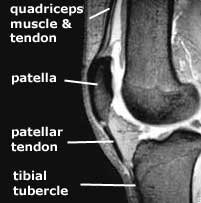

The term 'extensor mechanism' implies the unbroken chain of anatomical structures which cause the leg to extend -

The whole of this chain can be affected by the arthrofibrosis process.

The next thing that produces a loss of flexion that is very difficult to deal with is shortening of the quadriceps muscle. We documented in our studies that the quadriceps mechanism and the muscle actually shorten because scar tissue prohibits normal muscle contractions and lengthening. This muscle may start to shorten as early as four months following an injury or operation. And before that, the patellar tendon also will begin shorten, resulting in what is termed a patella infera condition.

Once the quadriceps muscle/patellar tendon mechanism goes through this shortening process, it is extremely difficult to recover the normal length. Once the surgeon has released all the tissues that I just mentioned above, the final thing that may still be limiting flexion is shortening in the quadriceps muscle and patellar tendon.

It is very difficult to measure how much shortening has occurred in the quadriceps tendon. The surgeon can get an idea if he or she can only flex the knee ninety to a hundred degrees for example. However, one can measure the amount of patellar tendon shortening using a method we published many years ago. A lateral x-ray is obtained of both knees and the height of the patella is measured, which allows interpretation of the length of the patellar tendon. The measurement of the involved knee is compared with the opposite knee, and the resulting difference indicates the amount of patella infera present.